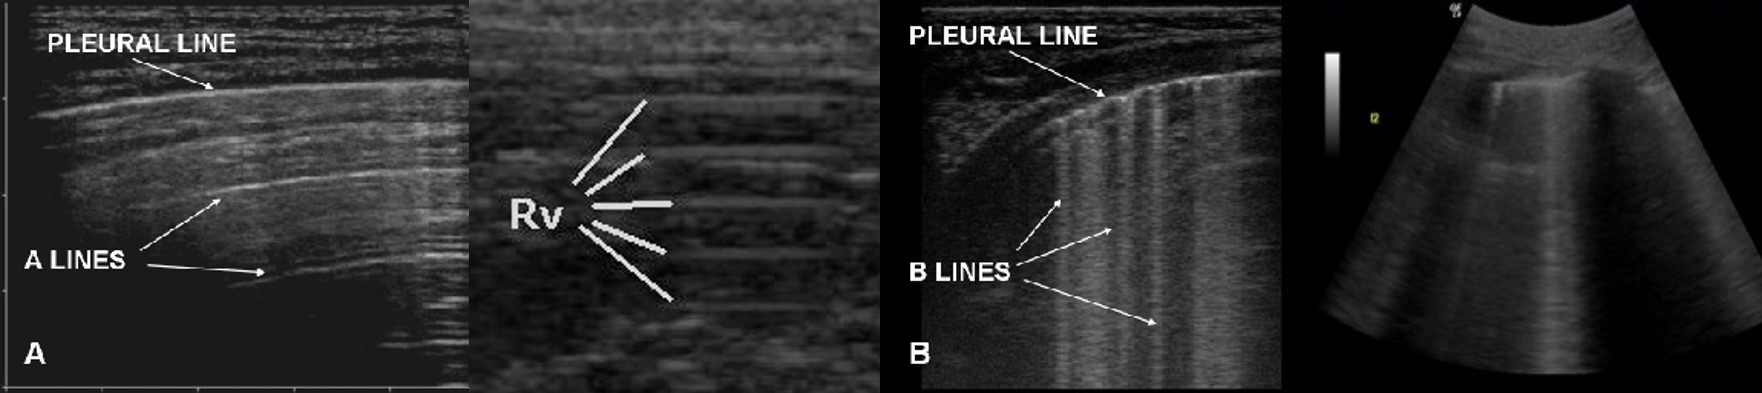

- Normal: vorderes Gleitzeichen + A-Lines (Reverbationen: Artefakt bei normaler Lungenlage)

- Lungenödem: multiple dominierende B-Lines (Wet-Lung: Discoscheinwerfer bei Lungenödem) + Gliding-Sign (Lunge gleitet auf Thoraxwand)

- Pneumothorax: kein vorderes Gliding-Sign + grobe A-Lines, kein Pleuralspalt, keine Kometenschweifartefakte